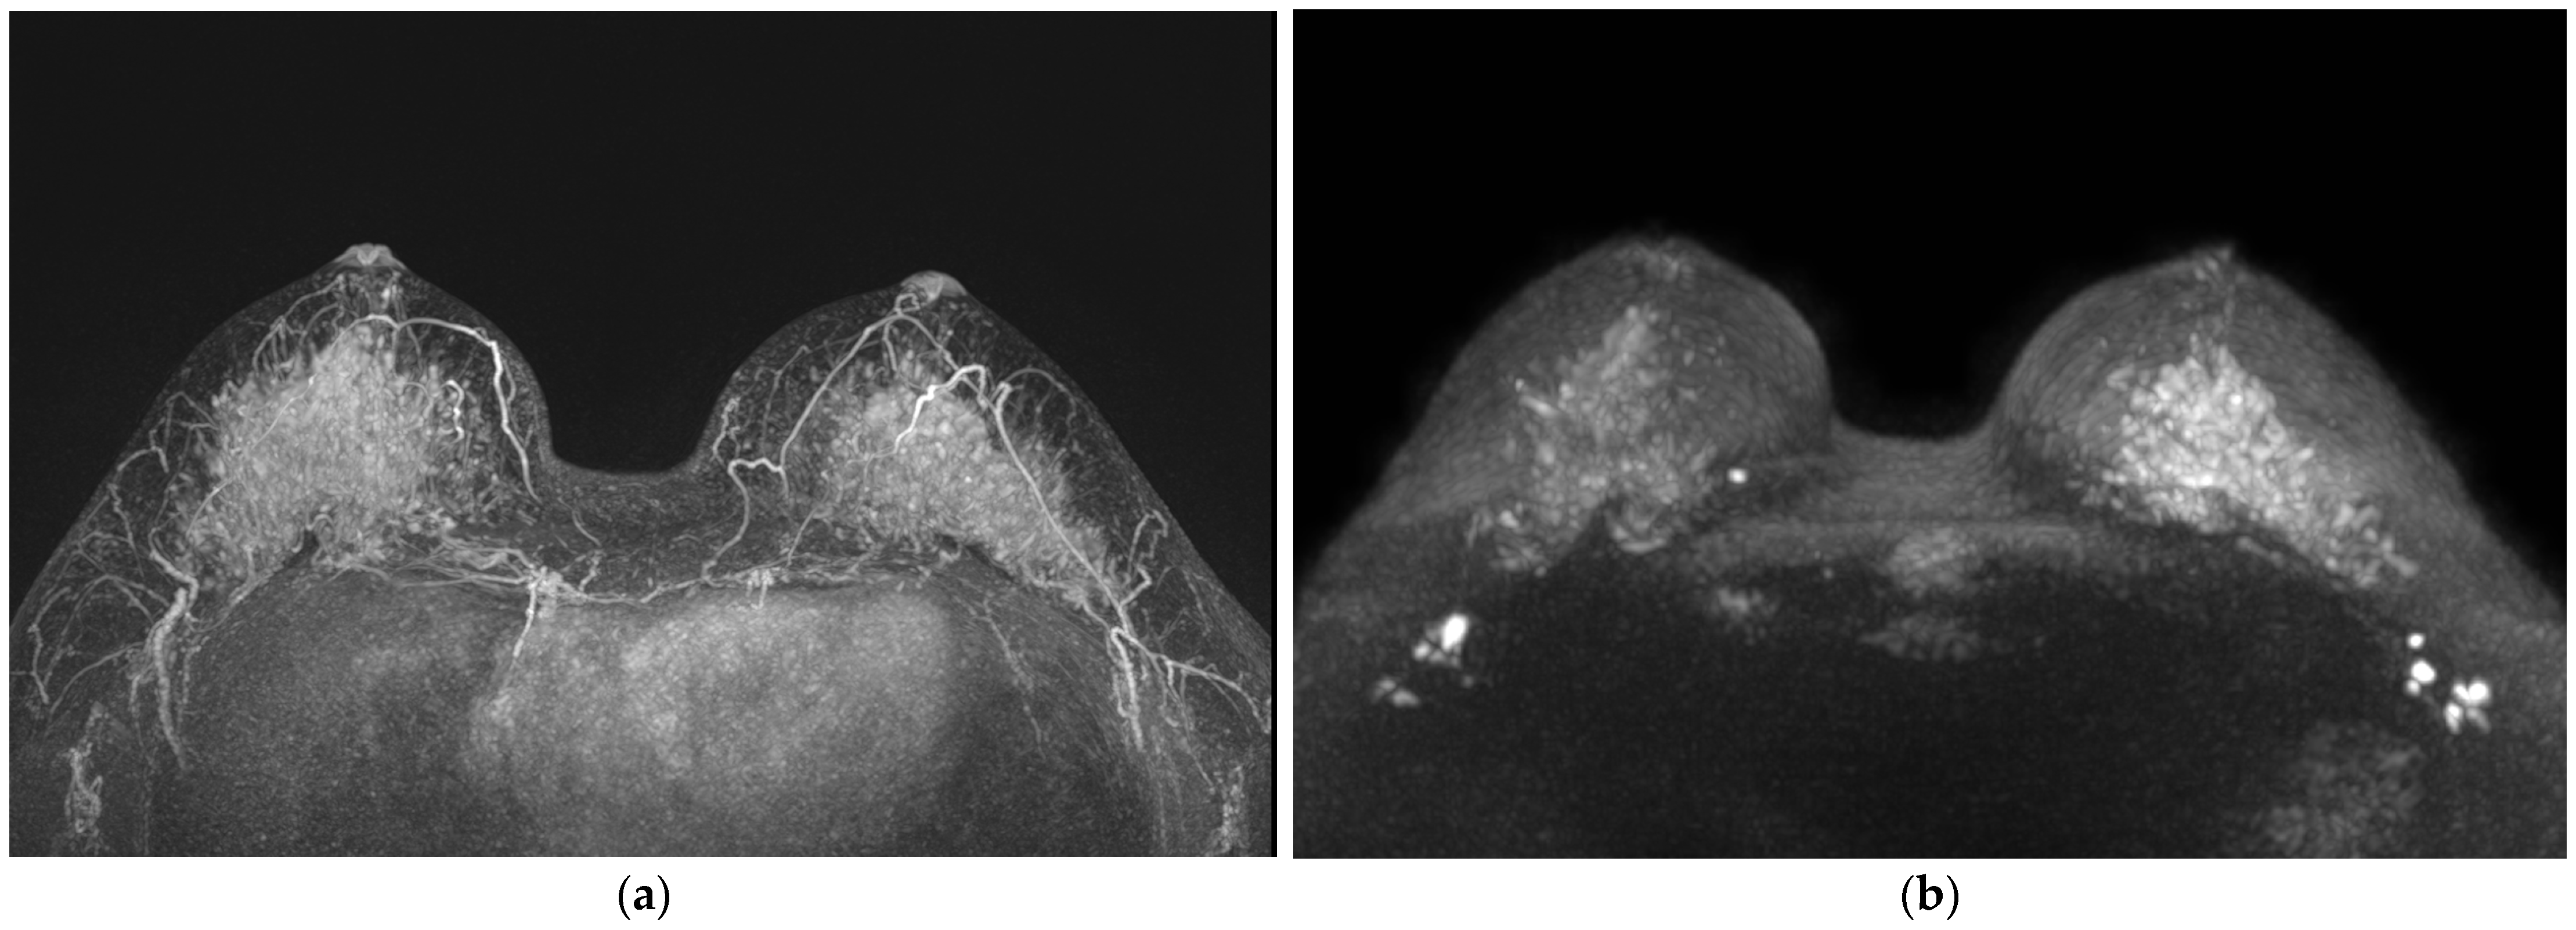

2.3. Image Analysis